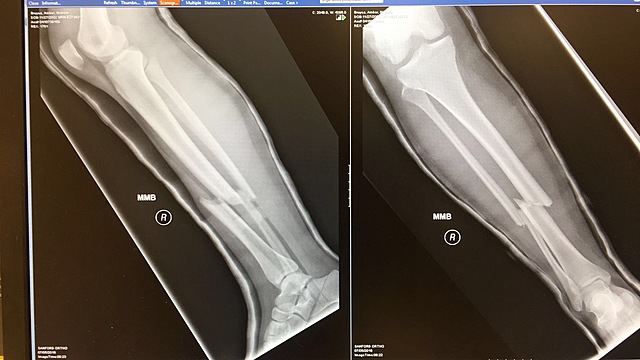

We as a team went to TNT gymnastics and they were doing skills and I already had those skills so I wanted to try some new ones. I was trying a new skills and I didn't land it and broke my right leg.

We went in for a check up on how my leg was doing and by the x-ray my leg had gotten worse. The cast wasn't doing my leg any good so the doctor said I had no choice but to get surgery.